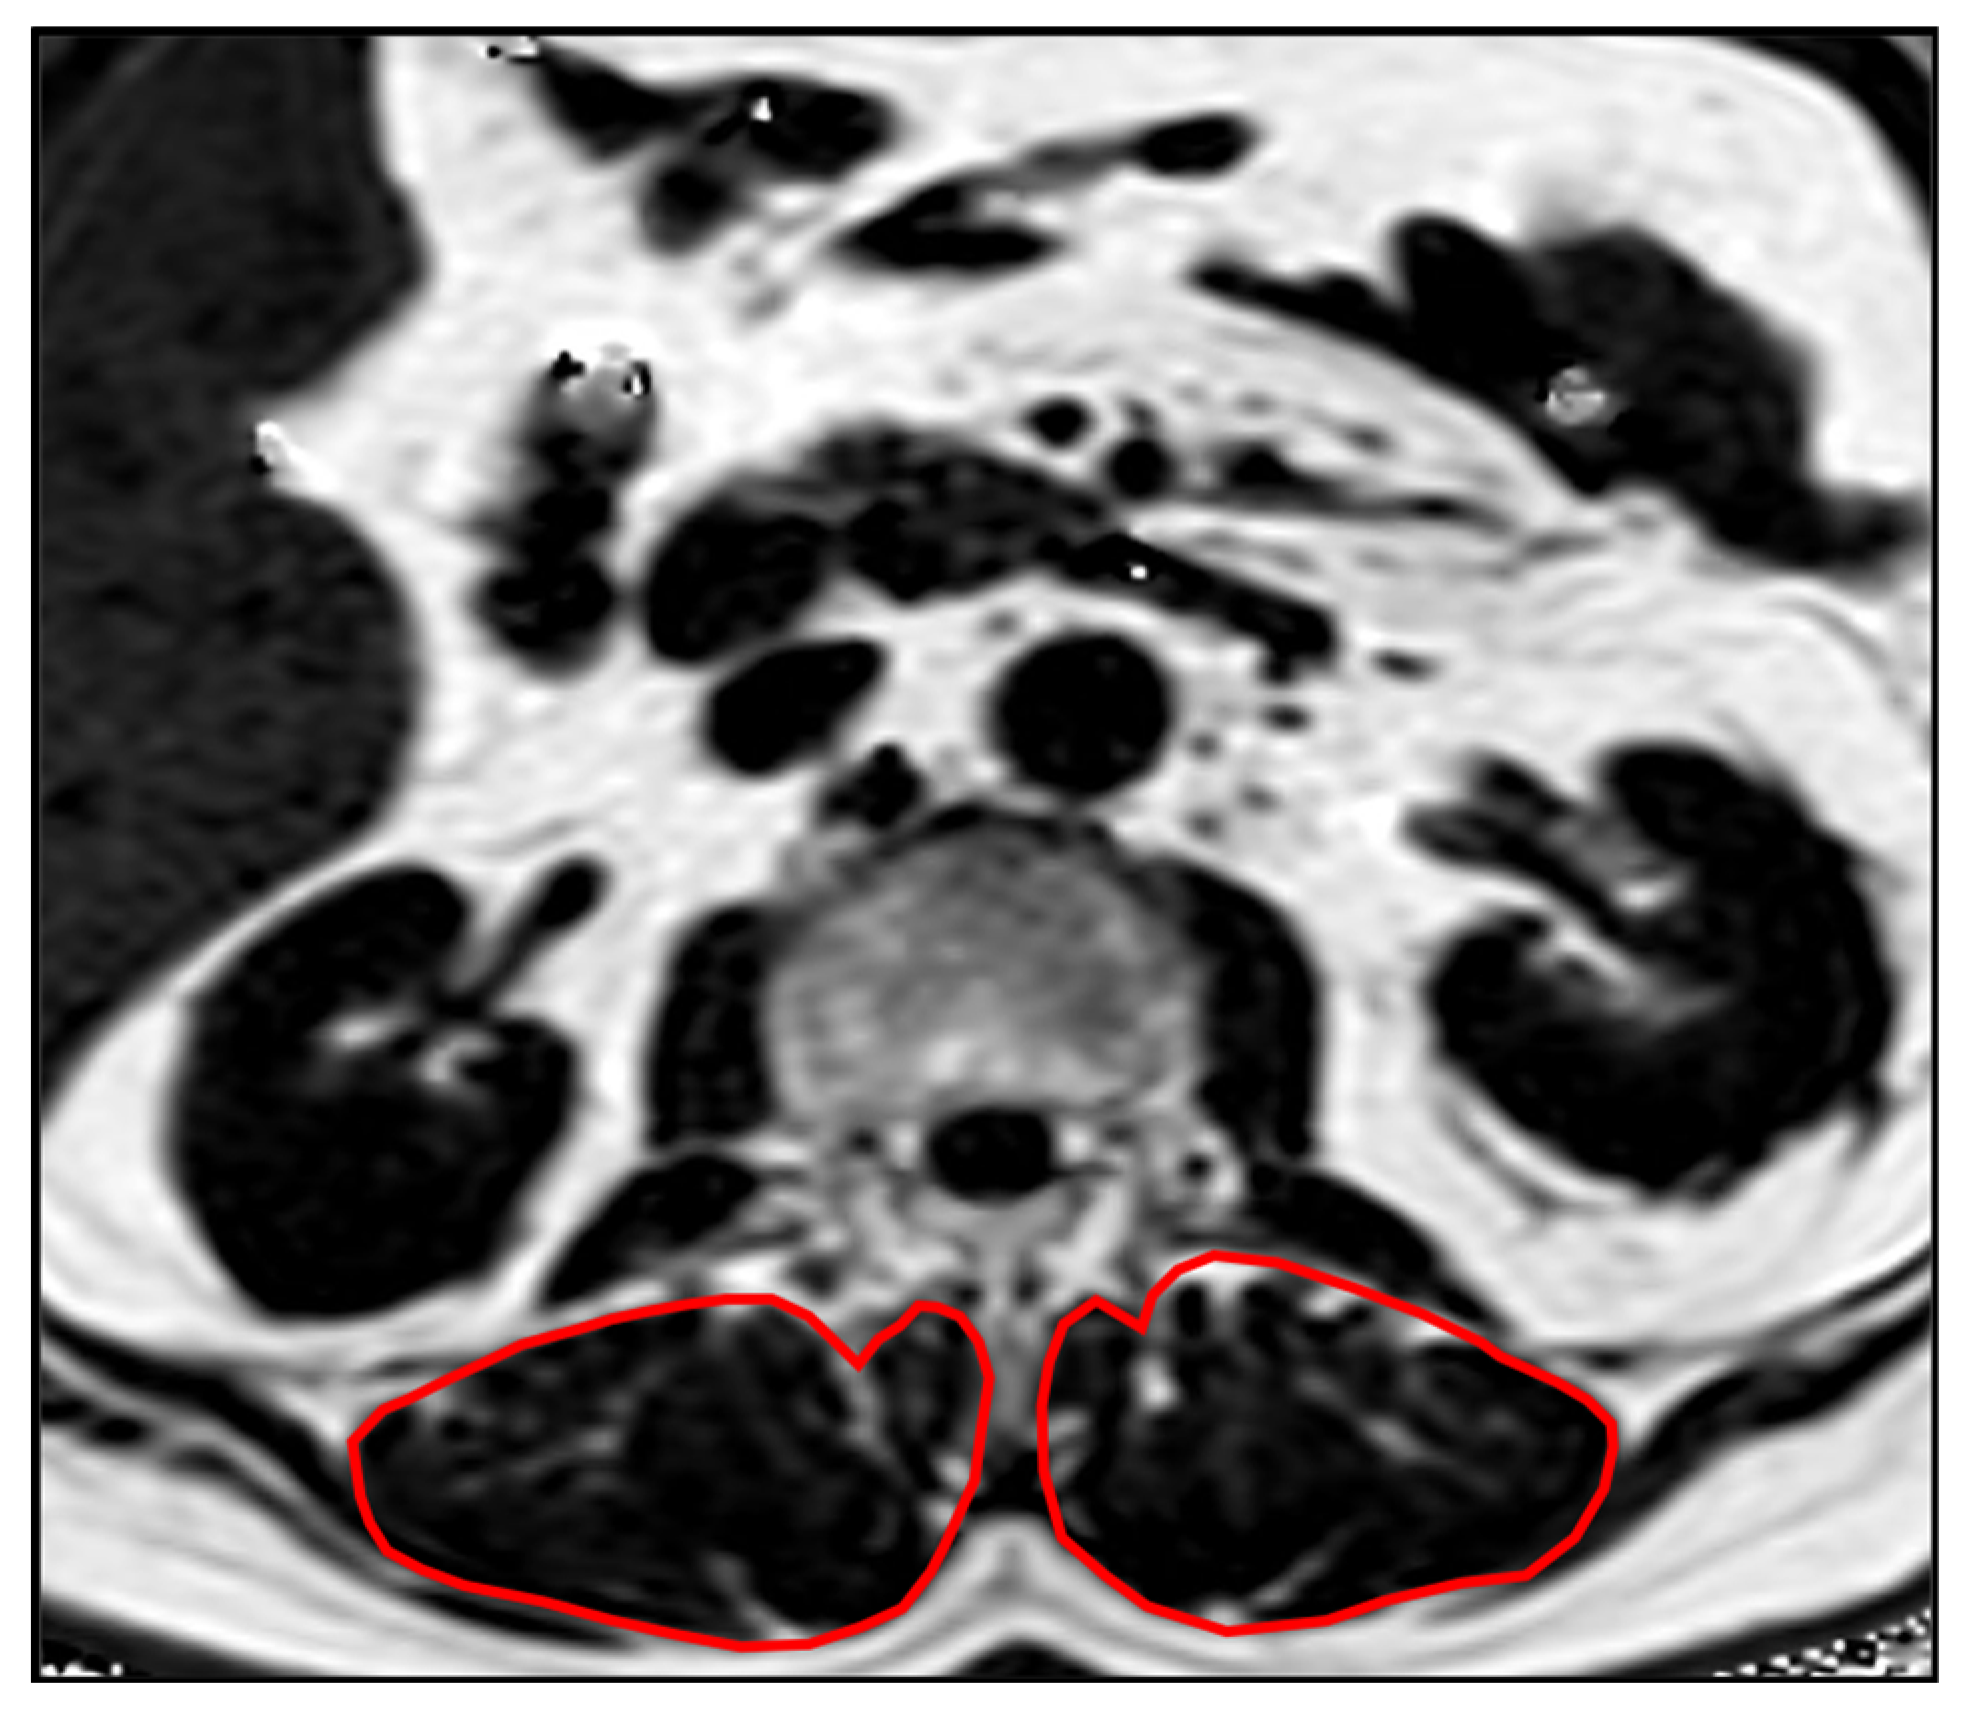

Segmentations of the lumbar vertebrae and the paraspinal muscles were performed manually by a radiologist (F.T.G., 5 years of experience in musculoskeletal imaging) on the PDFF and T2* maps using the IDS7 PACS (Sectra AB, Linkoeping, Sweden). Beginning in vertebra L1, 5 slices were segmented. The paraspinal musculature was segmented bilaterally and values of both sides were averaged (Figure 1). Segmentations were reviewed by a board-certified radiologist (A.S.G. with 9 years of experience in musculoskeletal imaging).

Figure 1.

Example PDFF map showing the segmentations of the PSM.